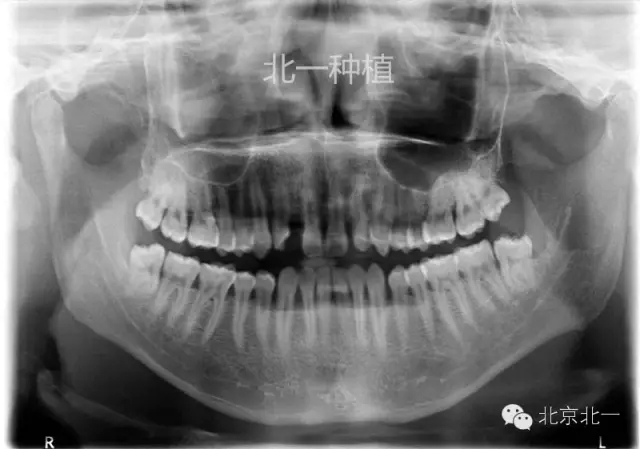

手術(shù)后拍全景片,順便把滯留乳牙拔除了。